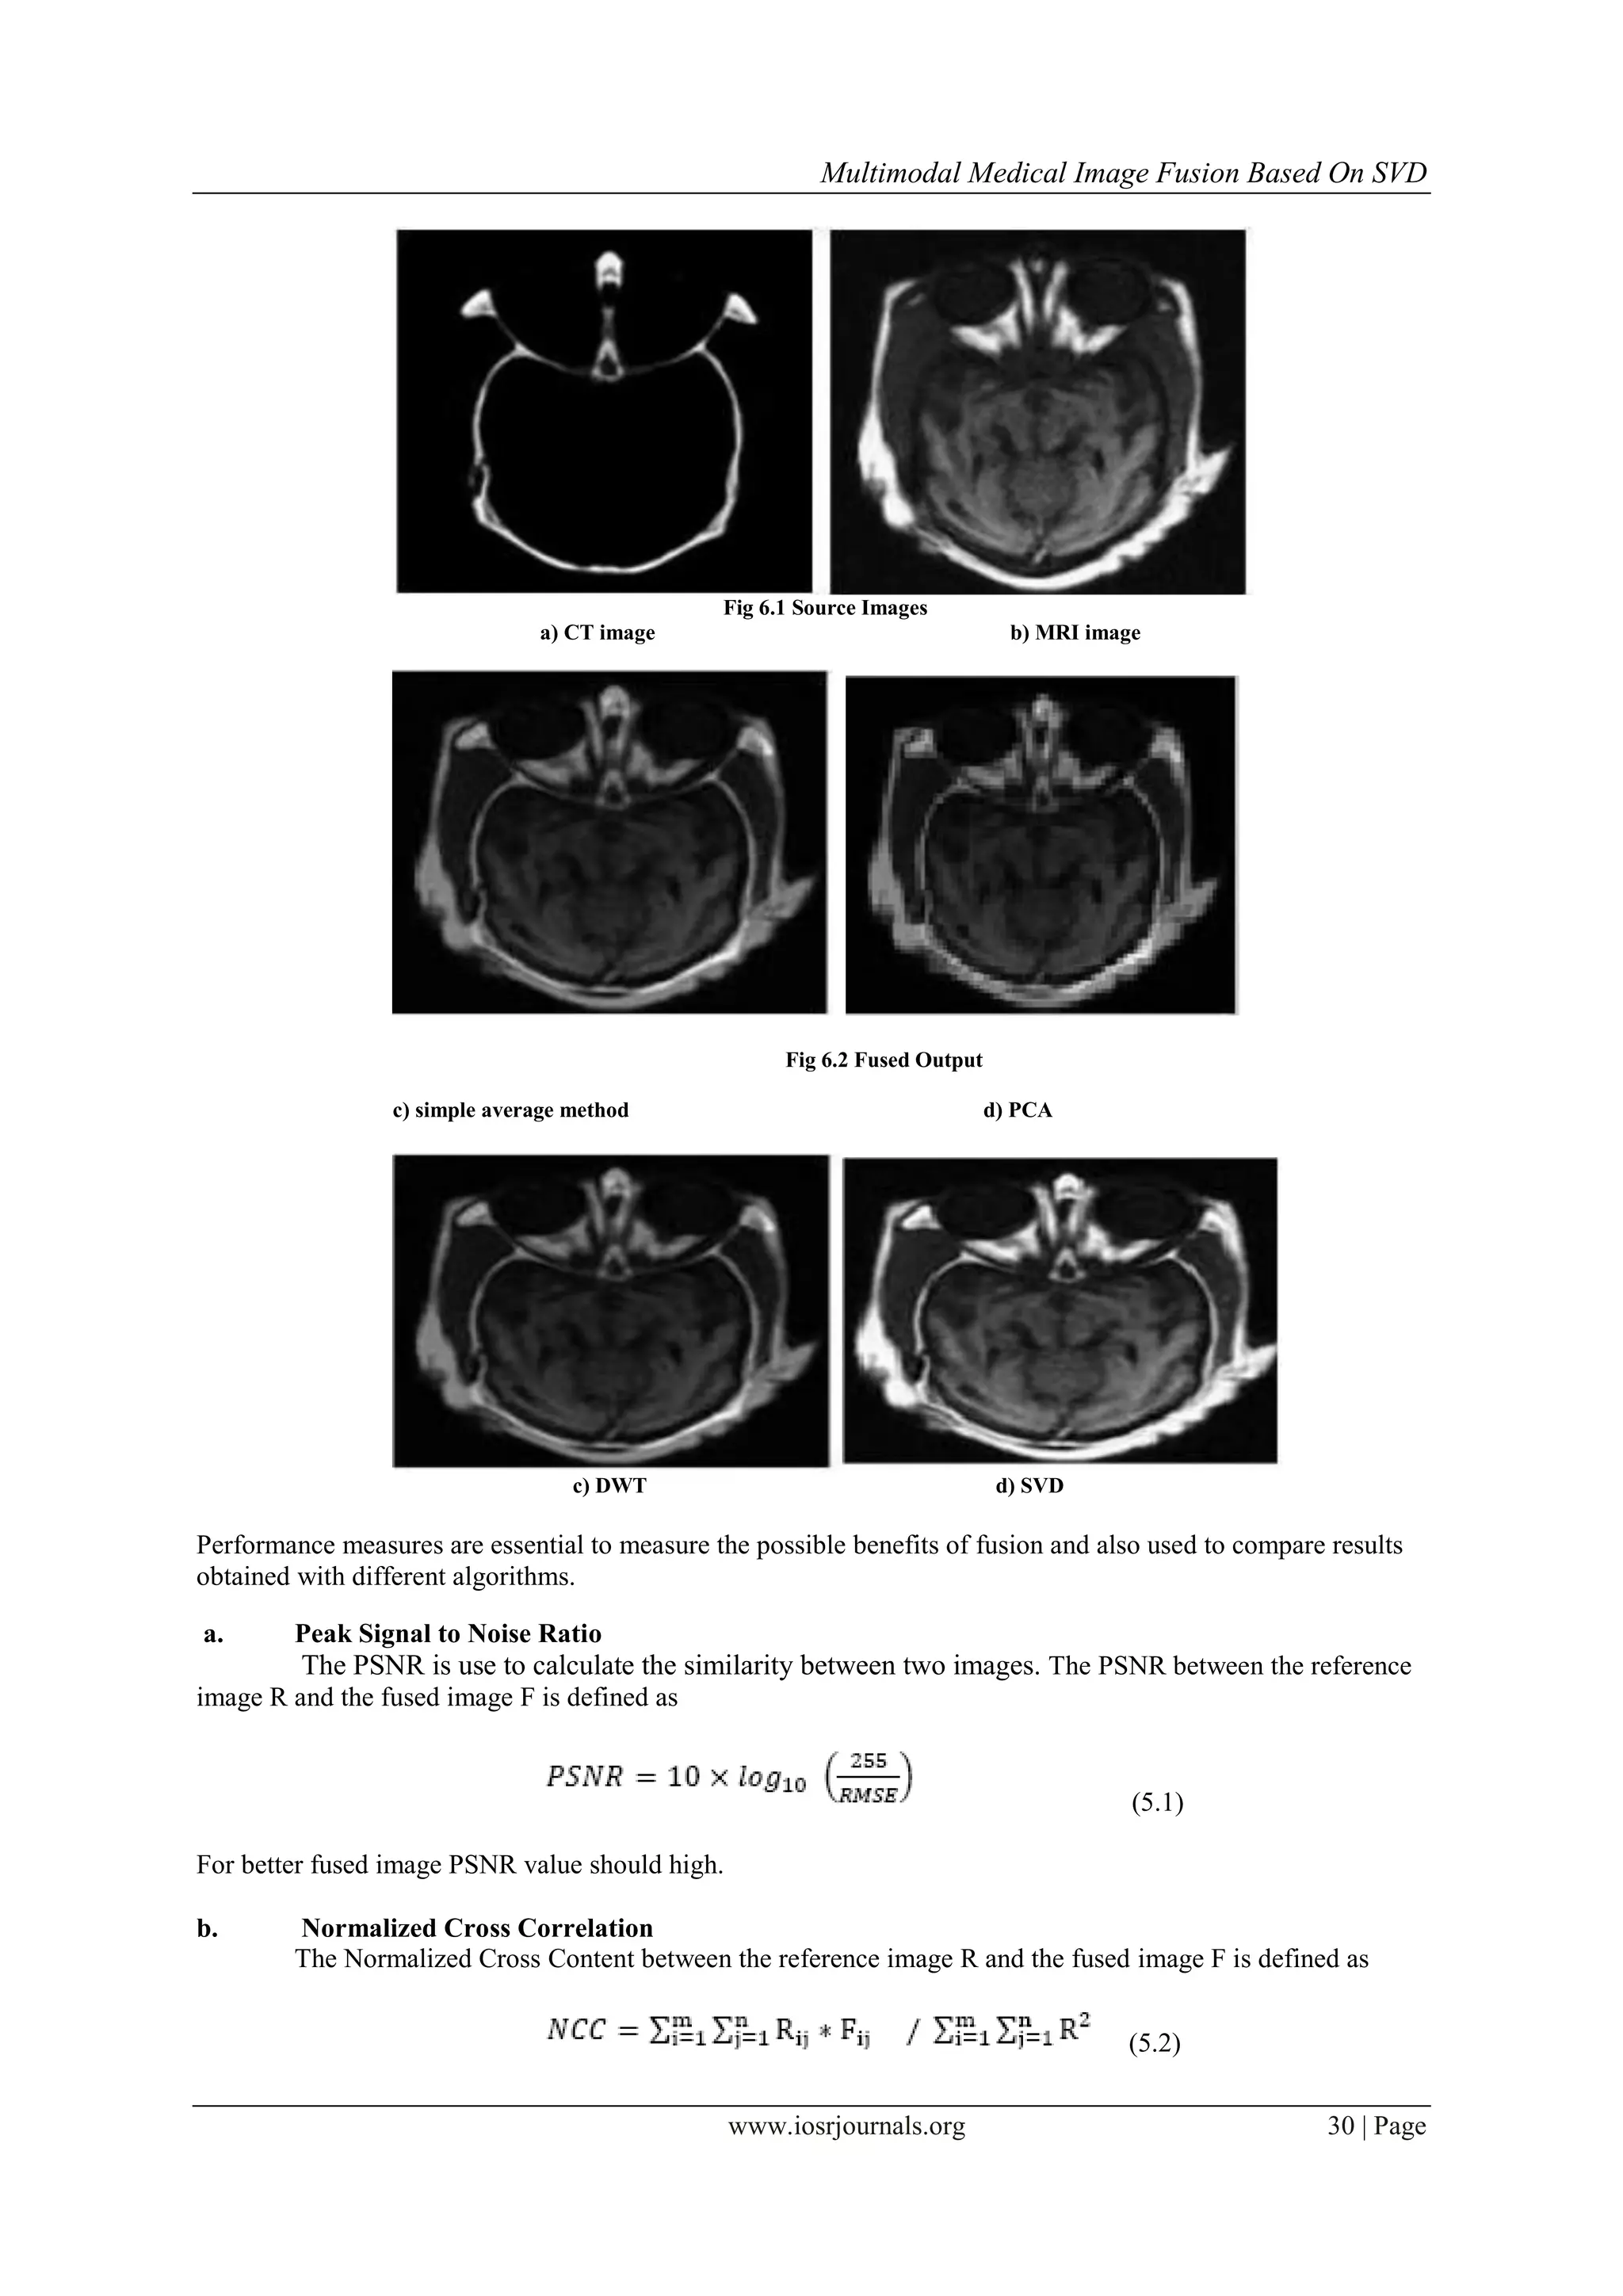

To verify the proposed method, it is tested on medical images. The general requirement of an image

should not introduce any distortion in resultant fused image.

Fig 6.1 Source Images

a) CT image b) MRI image

Fig 6.2 Fused Output

c) simple average method d) PCA

c) DWT d) SVD